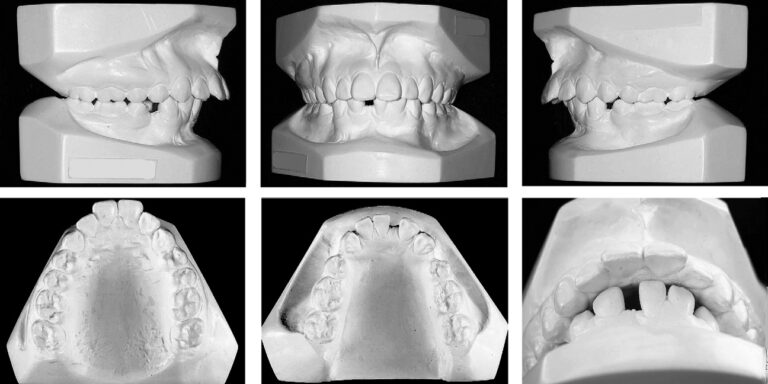

From a frontal view, her face was well balanced and symmetric (Fig 1). Her facial profile was convex, with an acute nasolabial angle, slight mandibular retrusion, strained lip seal, and normal vertical proportions. Intraorally, she had Angle Class I molar and Class II canine relationships on both sides. The maxillary midline was coincident with the facial midline, and both arch forms were ovoid. Her oral hygiene was excellent, with good periodontal health, and all restorations were satisfactory. She was congenitally missing a mandibular central incisor and had 2 nonerupted mandibular first premolars,

which were impacted by supernumerary teeth. Overbite was excessive (70%), overjet was 6 mm, and both mandibular and maxillary incisors were proclined (Fig 2).

Fig 2. Pretreatment study models.